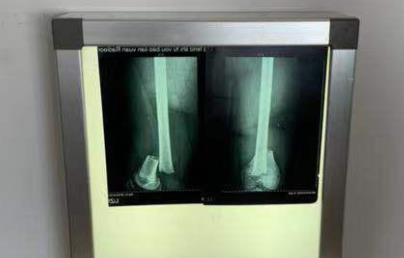

此前报道,因为上体育课与同学多讲了两句话,河南登封市少林延鲁武术学校一名初二学生李某屹被代课教练张某辉殴打,导致左股骨髁上骨折和左侧腓总神经损伤。事发后,10月18日,学校方面表示涉事教练目前已被停课,校方将积极配合警方调查,并组织涉事双方进行协商。

经查证, 9月21日下午17时许,因李某屹上课时与同学说话,被教练张某辉殴打。10月16日,经登封市公安局物证鉴定室鉴定【(登)公(刑)鉴(损伤)字[2019]595号】:李某屹左侧股骨下段骨折,左大腿的损伤程度为轻伤二级。